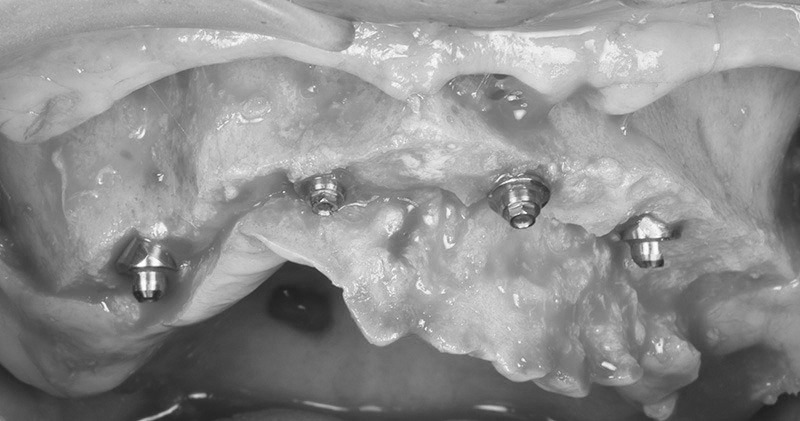

オールオン4を終えて

1st provisional restration

2nd provisional restration

術前の治療計画通りの位置に、インプラントを埋入する事が出来ました。

このように、ボーンリダクションを伴う、抜歯即時荷重症例において、Xガイドを用いることで、非常にシンプルな手術が行え、従来法(サージカルガイド)より正確な手術を行う事が可能となります。